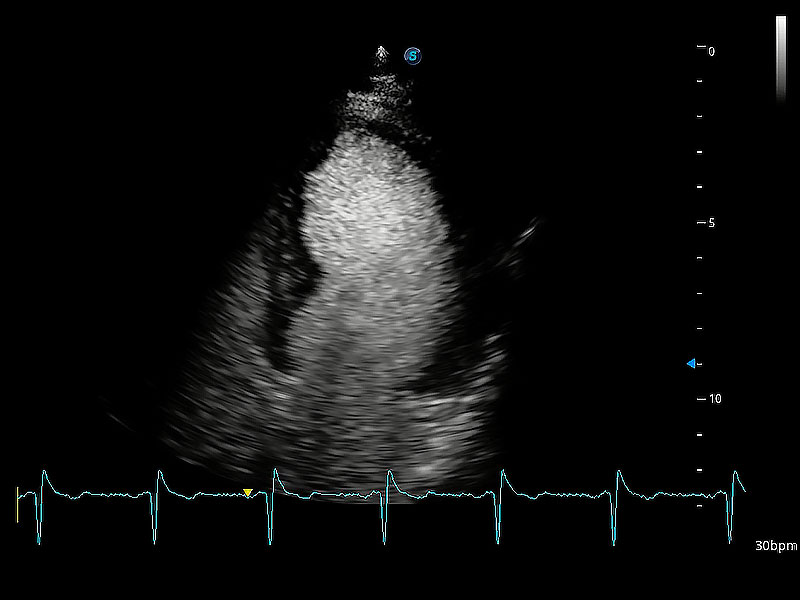

ProPet 80 配備了豐富的心臟探頭群、先進(jìn)的成像技術(shù)和專業(yè)的心臟測(cè)量工具,可幫助動(dòng)物醫(yī)生為不同體型和生理結(jié)構(gòu)的動(dòng)物提供心臟和心肌功能的全面評(píng)估。

通過360度任意調(diào)節(jié)3條M型取樣線,在同一心動(dòng)周期上觀察心臟不同位置的運(yùn)動(dòng)曲線,得到準(zhǔn)確的心功能測(cè)量數(shù)據(jù),有效評(píng)估心肌運(yùn)動(dòng)及左心室功能。